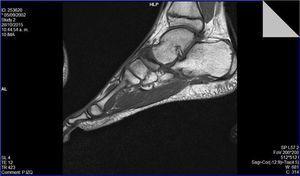

Una vez asintomático se inició de forma progresiva y controlada la actividad física. Inicialmente carrera en cinta desgravada, posteriormente en circuitos en campo para finalmente incorporarse a la rutina del equipo sin incidencias (Figura 4).

Figura 4. Resonancia magnética: secuencia potenciada en T1. Alteración en la morfología del escafoides tarsiano, con cambios artrósicos astragaloescafoideos.